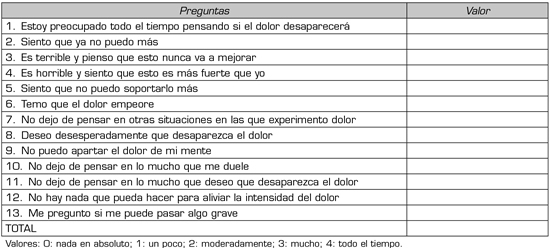

El catastrofismo, que es la percepción mental, negativa y exagerada, respecto a la experiencia dolorosa, tanto real como anticipada, se evaluó mediante la Escala de Catastrofismo validada en idioma español (10-12). Es un inventario de autoinforme que incluye 13 ítems (pensamientos catastróficos) que se agrupan en 3 factores, rumiación (preocupación constante e incapacidad de inhibir pensamientos relacionados con el dolor), magnificación (exageración de lo desagradable de las situaciones de dolor y de las expectativas de consecuencias negativas), y desesperanza (considerarse ineficaz para afrontar con éxito el dolor). El informante valora mediante un escala de Likert de 5 puntos, con valoración de 0 (nada en absoluto), 1 (un poco), 2 (moderadamente), 3 (mucho) y 4 (todo el tiempo) (Tabla I).

Tabla I. Formulario utilizado para la evaluación del catastrofismo, validado al idioma español.

El score total de la escala de catastrofismo (catastrofismo total) varía entre 0 y 52, indicando las puntuaciones bajas un escaso catastrofismo y las altas uno elevado. Un score de 30 se considera severo, y es indicativo de un nivel clínicamente relevante de catastrofismo (10,12).